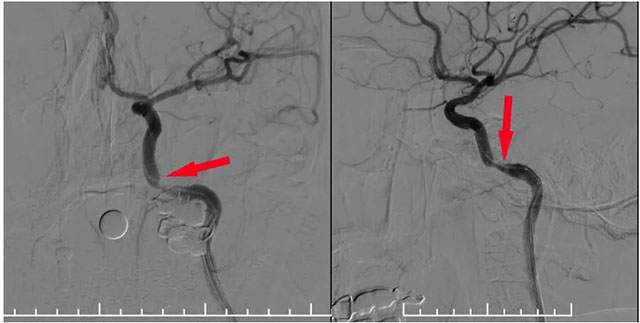

术中,张琪博士在刘春医生、周林华医生及医护团队协助下从左侧股动脉穿刺,置入6F导管鞘。将6F导引导管在泥鳅导丝导引下置入左侧颈内动脉,造影明确岩骨段狭窄呈,测量狭窄段长度及近远端血管支架,选择合适支架,随后在微导丝辅助下越过狭窄段超选至C6段,选用4.0*18球扩支架,沿微导丝到位狭窄段,球囊扩张至6atm,即刻释放支架,即刻造影见狭窄明显改善,支架贴壁良好,血流通畅,狭窄段完全覆盖。

▲ 球囊扩张支架在微导丝导引下到位于狭窄段

▲ 球囊扩张后支架释放狭窄已明显改善